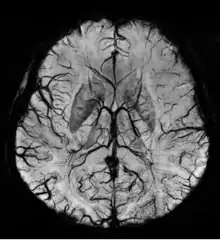

صورة الرنين المغناطيسي الموزنة بقابلية التمغنط

صورة الرنين المغناطيسي الموّزنة بقابلية التمغنط (Susceptibility weighted imaging (SWI ، بشكل عام تُسمّى BOLD venographic imaging -وهذا الاختصار يدل على أنها تعتمد على مستويات الأوكسوجين والدم في الأوردة-، تستخدم نوع من أنواع التباين في التصوير بالرنين المغناطيسي يختلف عن التباين التقليدي (كثافة البروتونات، T1 ، T2) ،تستخدم هذه التقنية تعويض التدفق لإلغاء أثر الدم المتحرك داخل الأوردة، التقاط الإشارة الراجعة على مدى وقت طويل، ونوع من أنواع السلاسل التصويرية يعتمد على التدرج الكهربائي في استخراج الصورة يُدعى gradient recalled echo (GRE) pulse sequence.[1] هذه الطريقة تستثمر الاختلاف بقابلية التمغنط بين الانسجة وتستخدم صورة الحالة (phase image) للكشف عن الاختلافات. تُدمج الصورة الكميّة (magnitude image) مع صورة الحالة (phase image) لإنتاج صورة كميّة مُحسّنة التباين التي تكون حساسة بشكل رائع للدم في الأوردة، النزيف و تخزين الحديد. نظراً لحساسيتها للدم في الأوردة تُستخدم هذه التقنية بشكل شائع عند المرضى المصابين بإصابات للدماغ نتيجة لضربات خارجية المصدر وتستخدم أيضاً لإستخراج صورة عالية الدقة لأوردة الدماغ ولها العديد من التطبيقات السريرية الأخرى. صورة الرنين المغناطيسي الموّزنة بقابلية التمغنط تُقدَّم كحزمة سريرية من شركة Philips و Siemens ولكن يُمكن أن تُشغل على أي آلة مُصنّعة على المجالات المغناطيسية بِقوة 1 تسلا، 1.5 تسلا، 3 تسلا وأعلى.